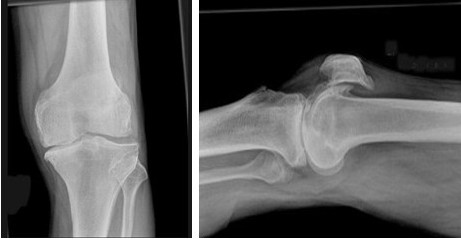

男,76岁,左膝关节长久站立时疼痛,可捫及捏发音,请结合图像,选出最可能的诊断

A:退行性骨关节病

B:畸形性骨炎

C:神经性关节病

D:创伤性关节炎

E:肥大性骨关节病